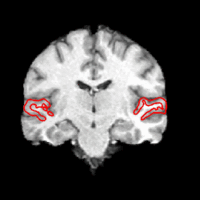

TGIt.gif

Joint Segmentation of Image Ensembles via Latent Atlases

Spatial priors, such as probabilistic atlases, play an important role in MRI segmentation. The atlases are typically generated by averaging manual labels of aligned brain regions across different subjects. However, the availability of comprehensive, reliable and suitable manual segmentations is limited. We therefore propose a joint segmentation of corresponding, aligned structures in the entire population that does not require a probability atlas. More...